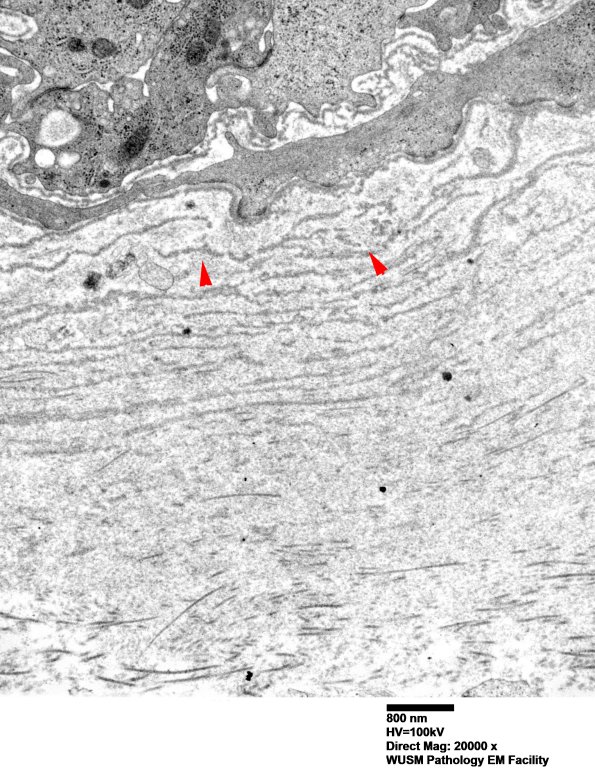

Thickening of this vessel wall consists of accumulated basal lamina fragments (arrowheads, 6C3) and collagen. (electron micrographs)